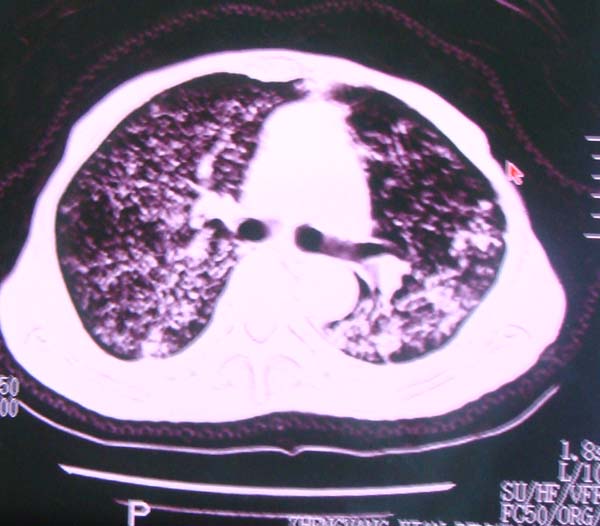

以下是引用zhangzhongshou在2008-2-15 22:25:00的发言:[br]片子照得不清,基本考虑1、细支气管肺泡癌2、亚急性血行播散型肺结核。请结合临床。片子细节显示不清,无法提供进一步意见。

以下是引用杀毒软件在2008-2-15 22:34:00的发言:[br]小叶中心性肺气肿。两肺弥漫性病变,肺泡微石病,过敏性肺炎,尘肺2期,特发性肺纤维化都有可能。[br]不象肺泡癌。